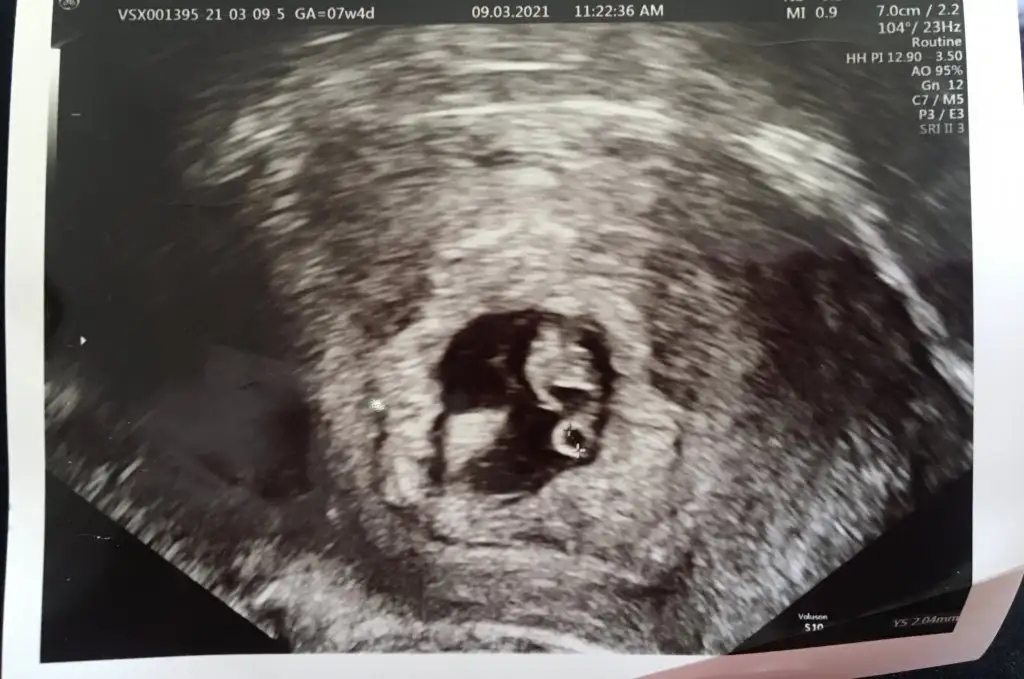

7+4 olduk bugün.

O devasa kanamadan sonra düşüğü kabullendik derken kalp atışını duymuştuk. Bugün daha büyümüş gördük. Kalbi hala gümbür gümbür. Kanama alanı var, benim kahverengi akıntım 13 gündür devam ediyor. Bu bebek doğarsa literatüre geçersin dedi doktor

Fotoğrafları paylaştım vajinal ultrason. Kalbi 140 üzerinde atıyor. Kesenin solunda, kese içine doğru kanama alanı varmış allahtan bebeği sıkıştırmıyor. Yorumlayacak olan var mı?